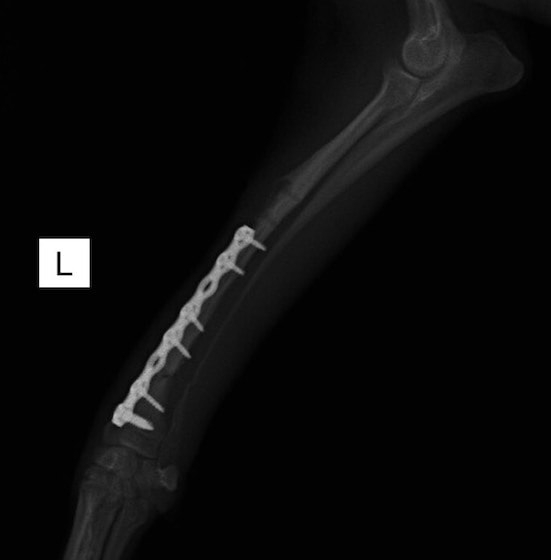

トイプードル 右遠位橈尺骨短斜骨折のALPSによる内固定

当院ではAdvanced Locking plate system(ALPS)と、Locking compression plate system(LCPS)という骨接合法で骨折症例の治療を行っています。

LCPは、スクリュー(ネジ)とプレート(金属の板)をロックする特殊な構造により骨折部位を固定する新しい世代のプレートシステムです。ひとつのホールでロッキングスクリューとスタンダードスクリューの使用を選択できるユニークな構造をしているため、骨折断端間の圧迫を目的とした従来型プレート固定法に加え、高い角度安定性を有するロッキングスクリューを用いた固定法の選択が可能です。従来のプレートシステムでは困難だった部分の骨折や癒合不全の症例に高い治療効果をもたらします。

従来型のプレートのように広い面積で骨と接するプレートを用いて固定を行った場合、プレート下の骨はプレートとの接触面において血行が絶たれ壊死し、それがリモデリングされると骨密度が低下する。この骨密度の低下防ぐために、骨折部局所への血行を温存することの重要性が近年改めて認識されるようになってきている。Advaed Locking Plate System (ALPS)は従来型のプレートシステムの欠点を改良し、より使いやすく、より骨への血行を阻害しないようにというコンセプトで作られた。